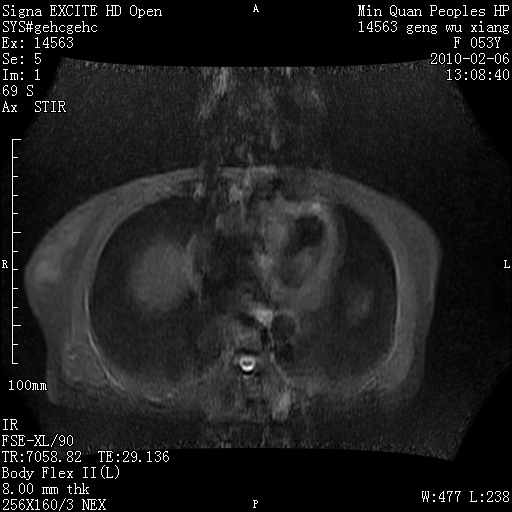

标题: MRI2762:胆道梗阻原因?

f,53y,全身黄染多日。

高位胆道梗阻 胆管癌可能性大

支持 高位胆道梗阻 胆管癌可能性大。